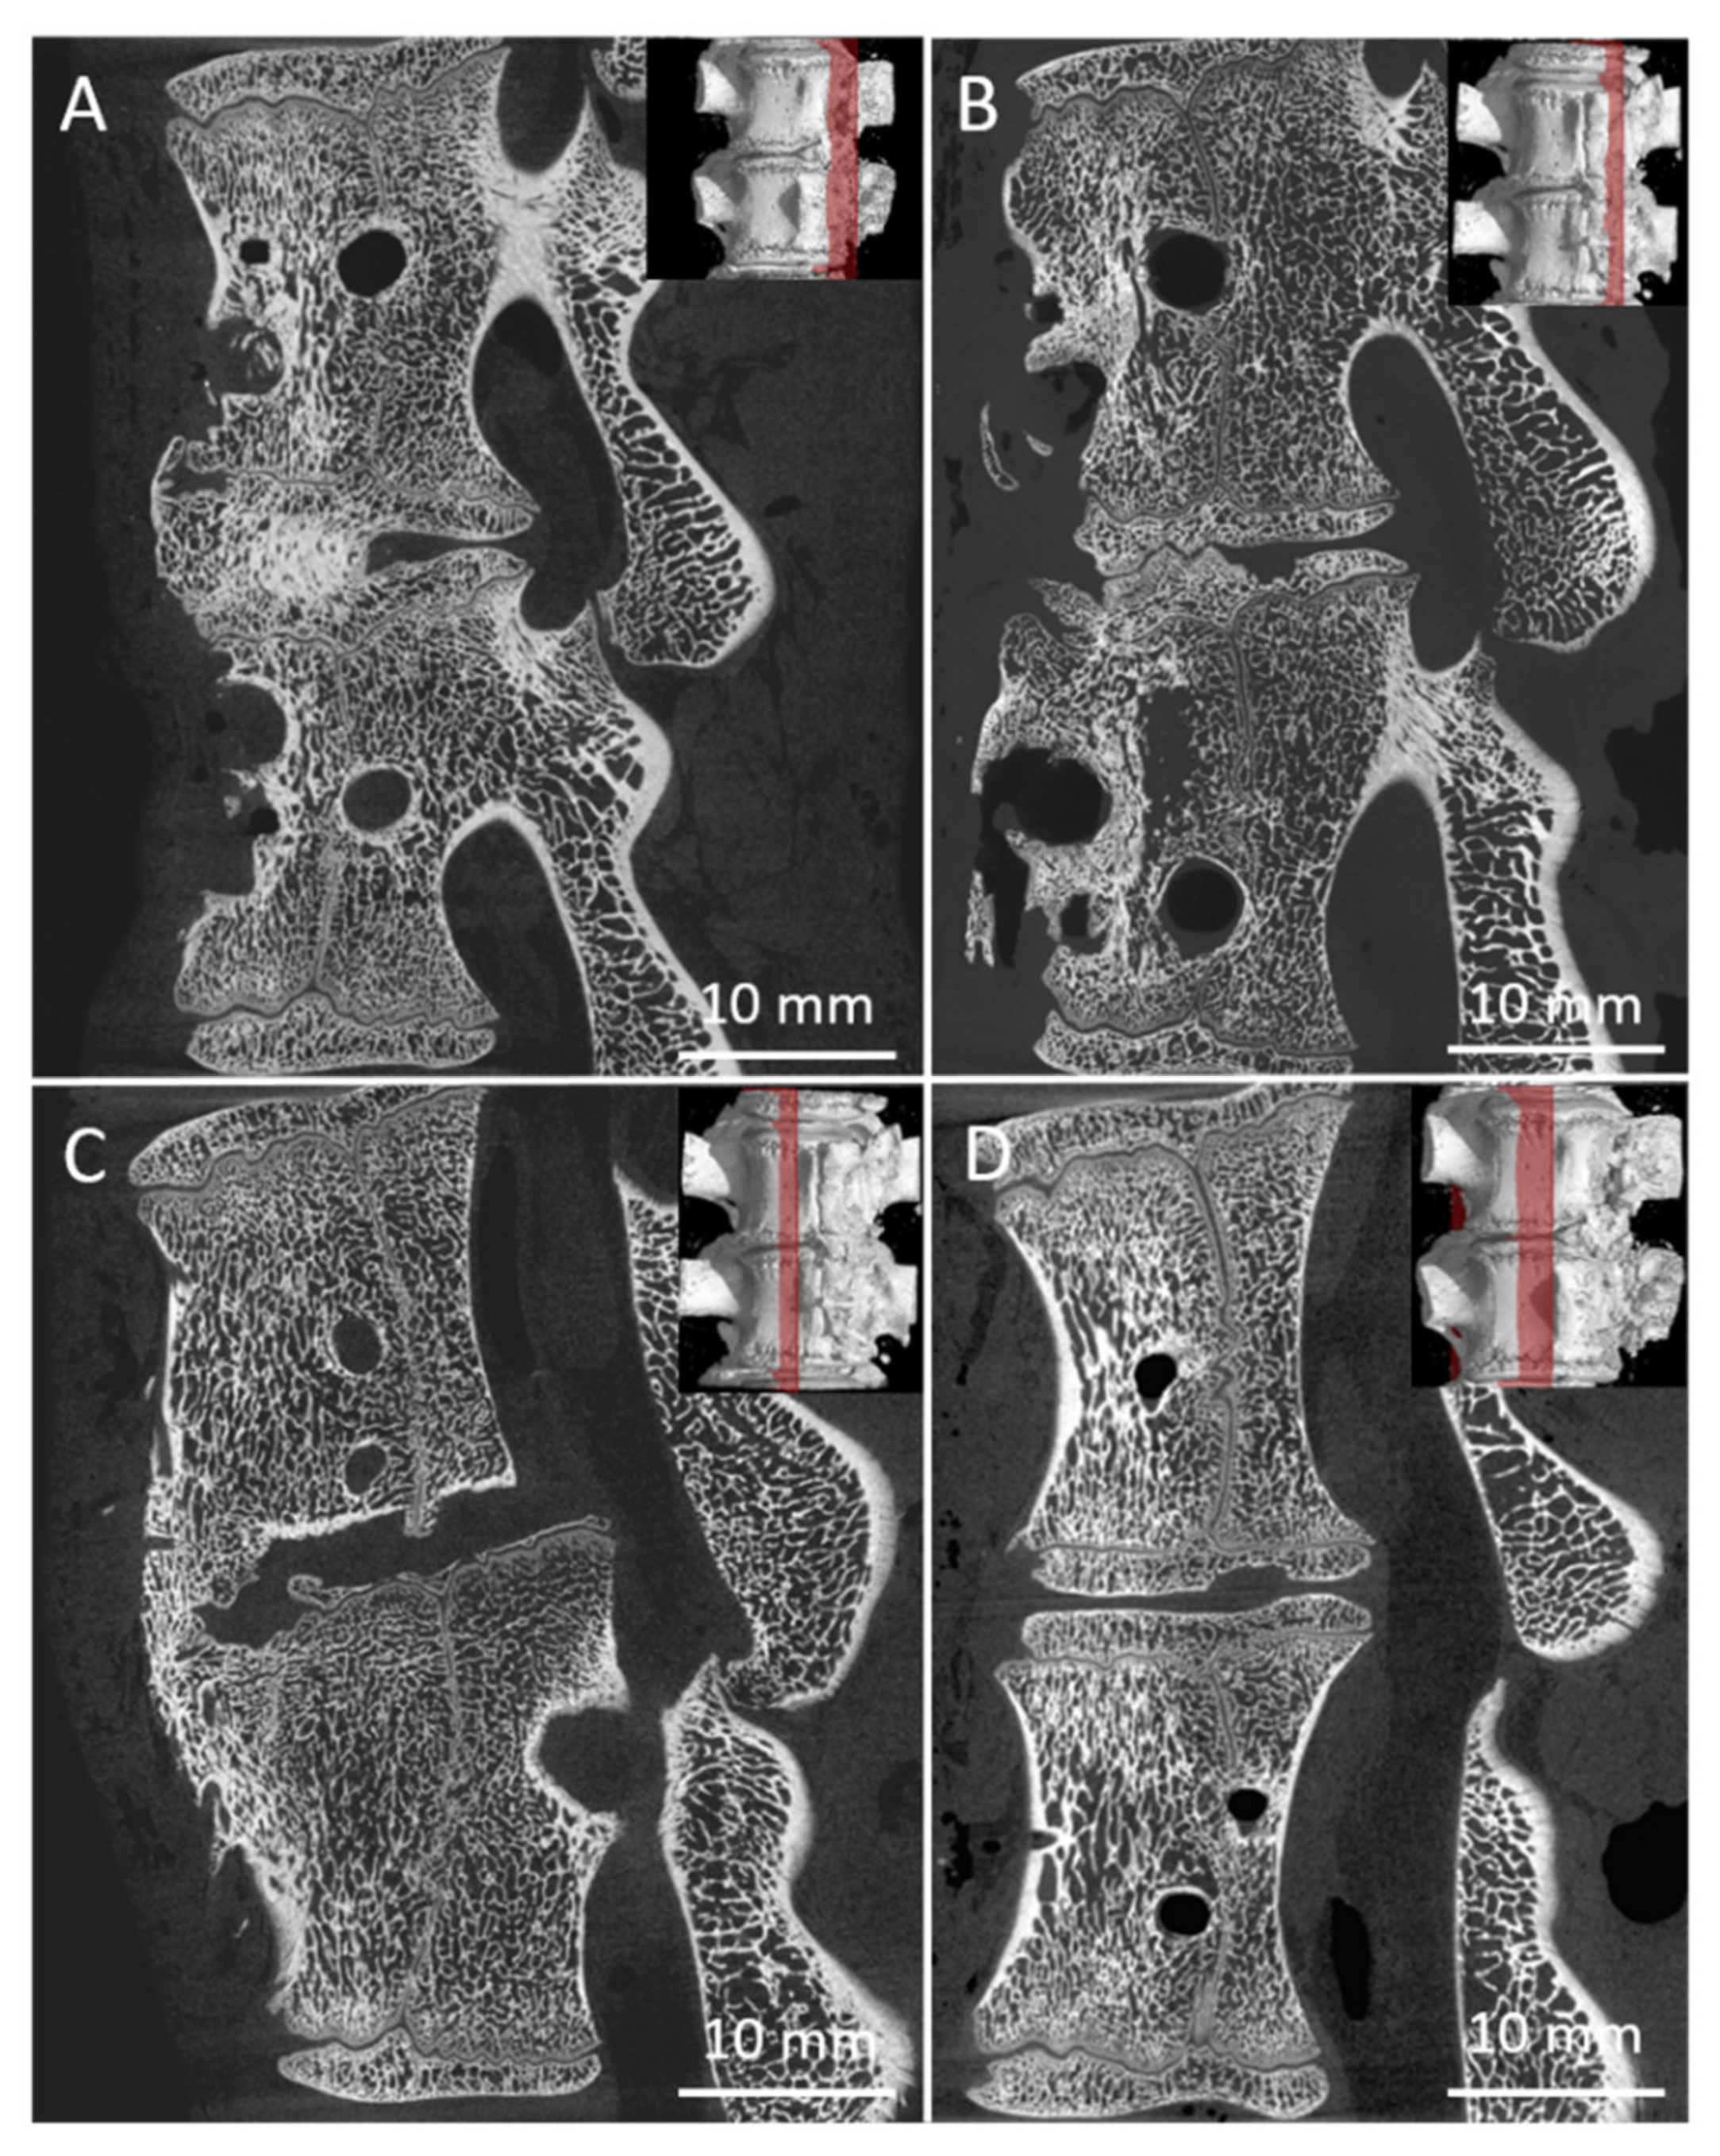

3.4. Micro-CT

3.5. Histology